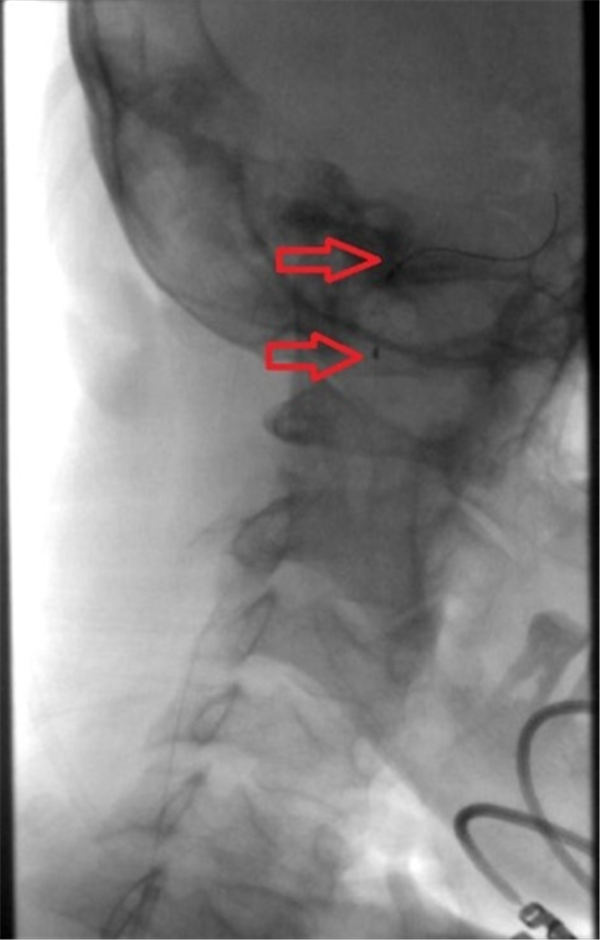

当天,老杜就顺利入住北京燕化医院,第三天就安排了介入手术:在右侧腹股沟局麻之后,穿刺股动脉插管到主动脉,再选择到右侧颈动脉造影,可见右侧颈内动脉重度狭窄、几近闭塞(上图红色箭头)。

确定狭窄部位之后,在微导丝的引导之下,小心的将保护伞(上图红色箭头之间)置于狭窄段远端,以阻拦可能脱落的斑块,避免术中脑梗塞的发生,手术结束之后再将保护伞回收。